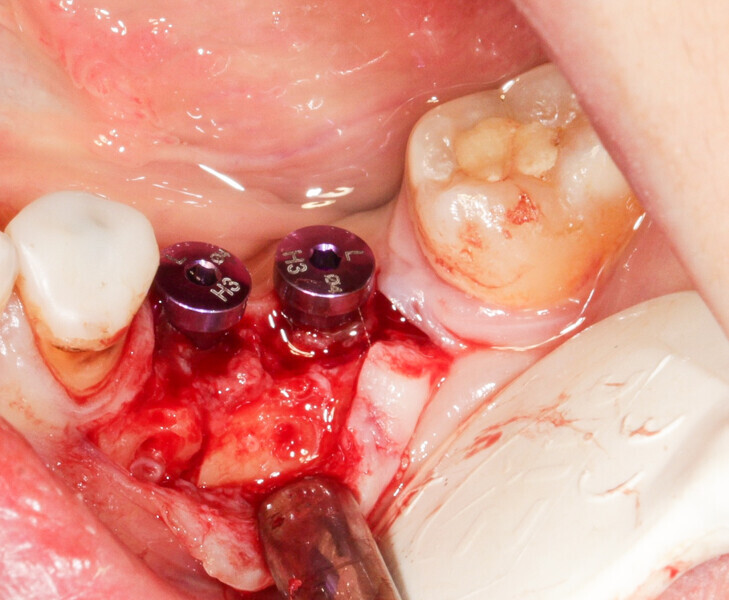

We had three alternative courses of action: a bone block graft from the mandibular ramus,2 a segmental osteotomy4 or a radicular graft, knowing that tooth #46 could not be saved. We chose the third option because it allowed for simultaneous implant placement and bone reconstruction. A large flap was elevated to assess the gap in the bone and in anticipation of closing the flap on an augmented ridge. Two implants were placed as normal despite the low residual bone thickness in the vestibular area of the planned positions for the implants (Fig. 5). The roots of tooth #46 were extracted atraumatically (root separation, use of piezo-surgery, etc.) and were then prepared as described. The roots were shaped to fit the defect and fixated at the insertion site using osteosynthesis screws (Fig. 6).3 The flap was mobilised and stretched to achieve edge-to-edge closure without tension, and a 4/0 rapidly resorbed braided thread was used for the sutures (Fig. 7). Four months after the bone augmentation and implant placement, healing abutments were connected to the implants and the osteosynthesis screws removed (Figs. 8 & 9). During the operation, time was taken to perform a visual check that ankylosis of the radicular grafts had been successful and that these were sound. Finally, a CBCT assessment was performed. The prosthesis was fitted by our colleague a few weeks later, once the soft tissue had healed.